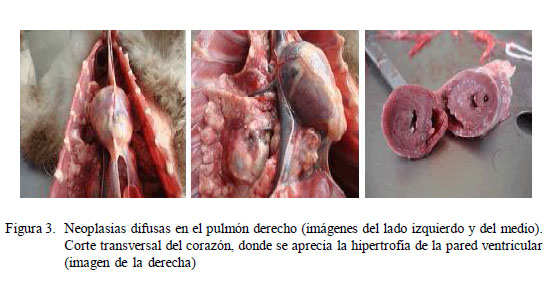

En la necropsia, la cavidad torácica presentó neoplasias difusas en los lóbulos apical, cardiaco y diafragmático del pulmón derecho y aumento del tamaño cardiaco, principalmente de la aurícula y ventrículo izquierdo. Al corte del corazón se evidenció hipertrofia de la pared ventricular izquierda (Fig 3). Se hizo un corte longitudinal en las arterias aorta e iliacas en la cavidad abdominal y se ubicó el trombo a nivel caudal de la bifurcación de la aorta, en la arteria iliaca derecha (Fig 4).